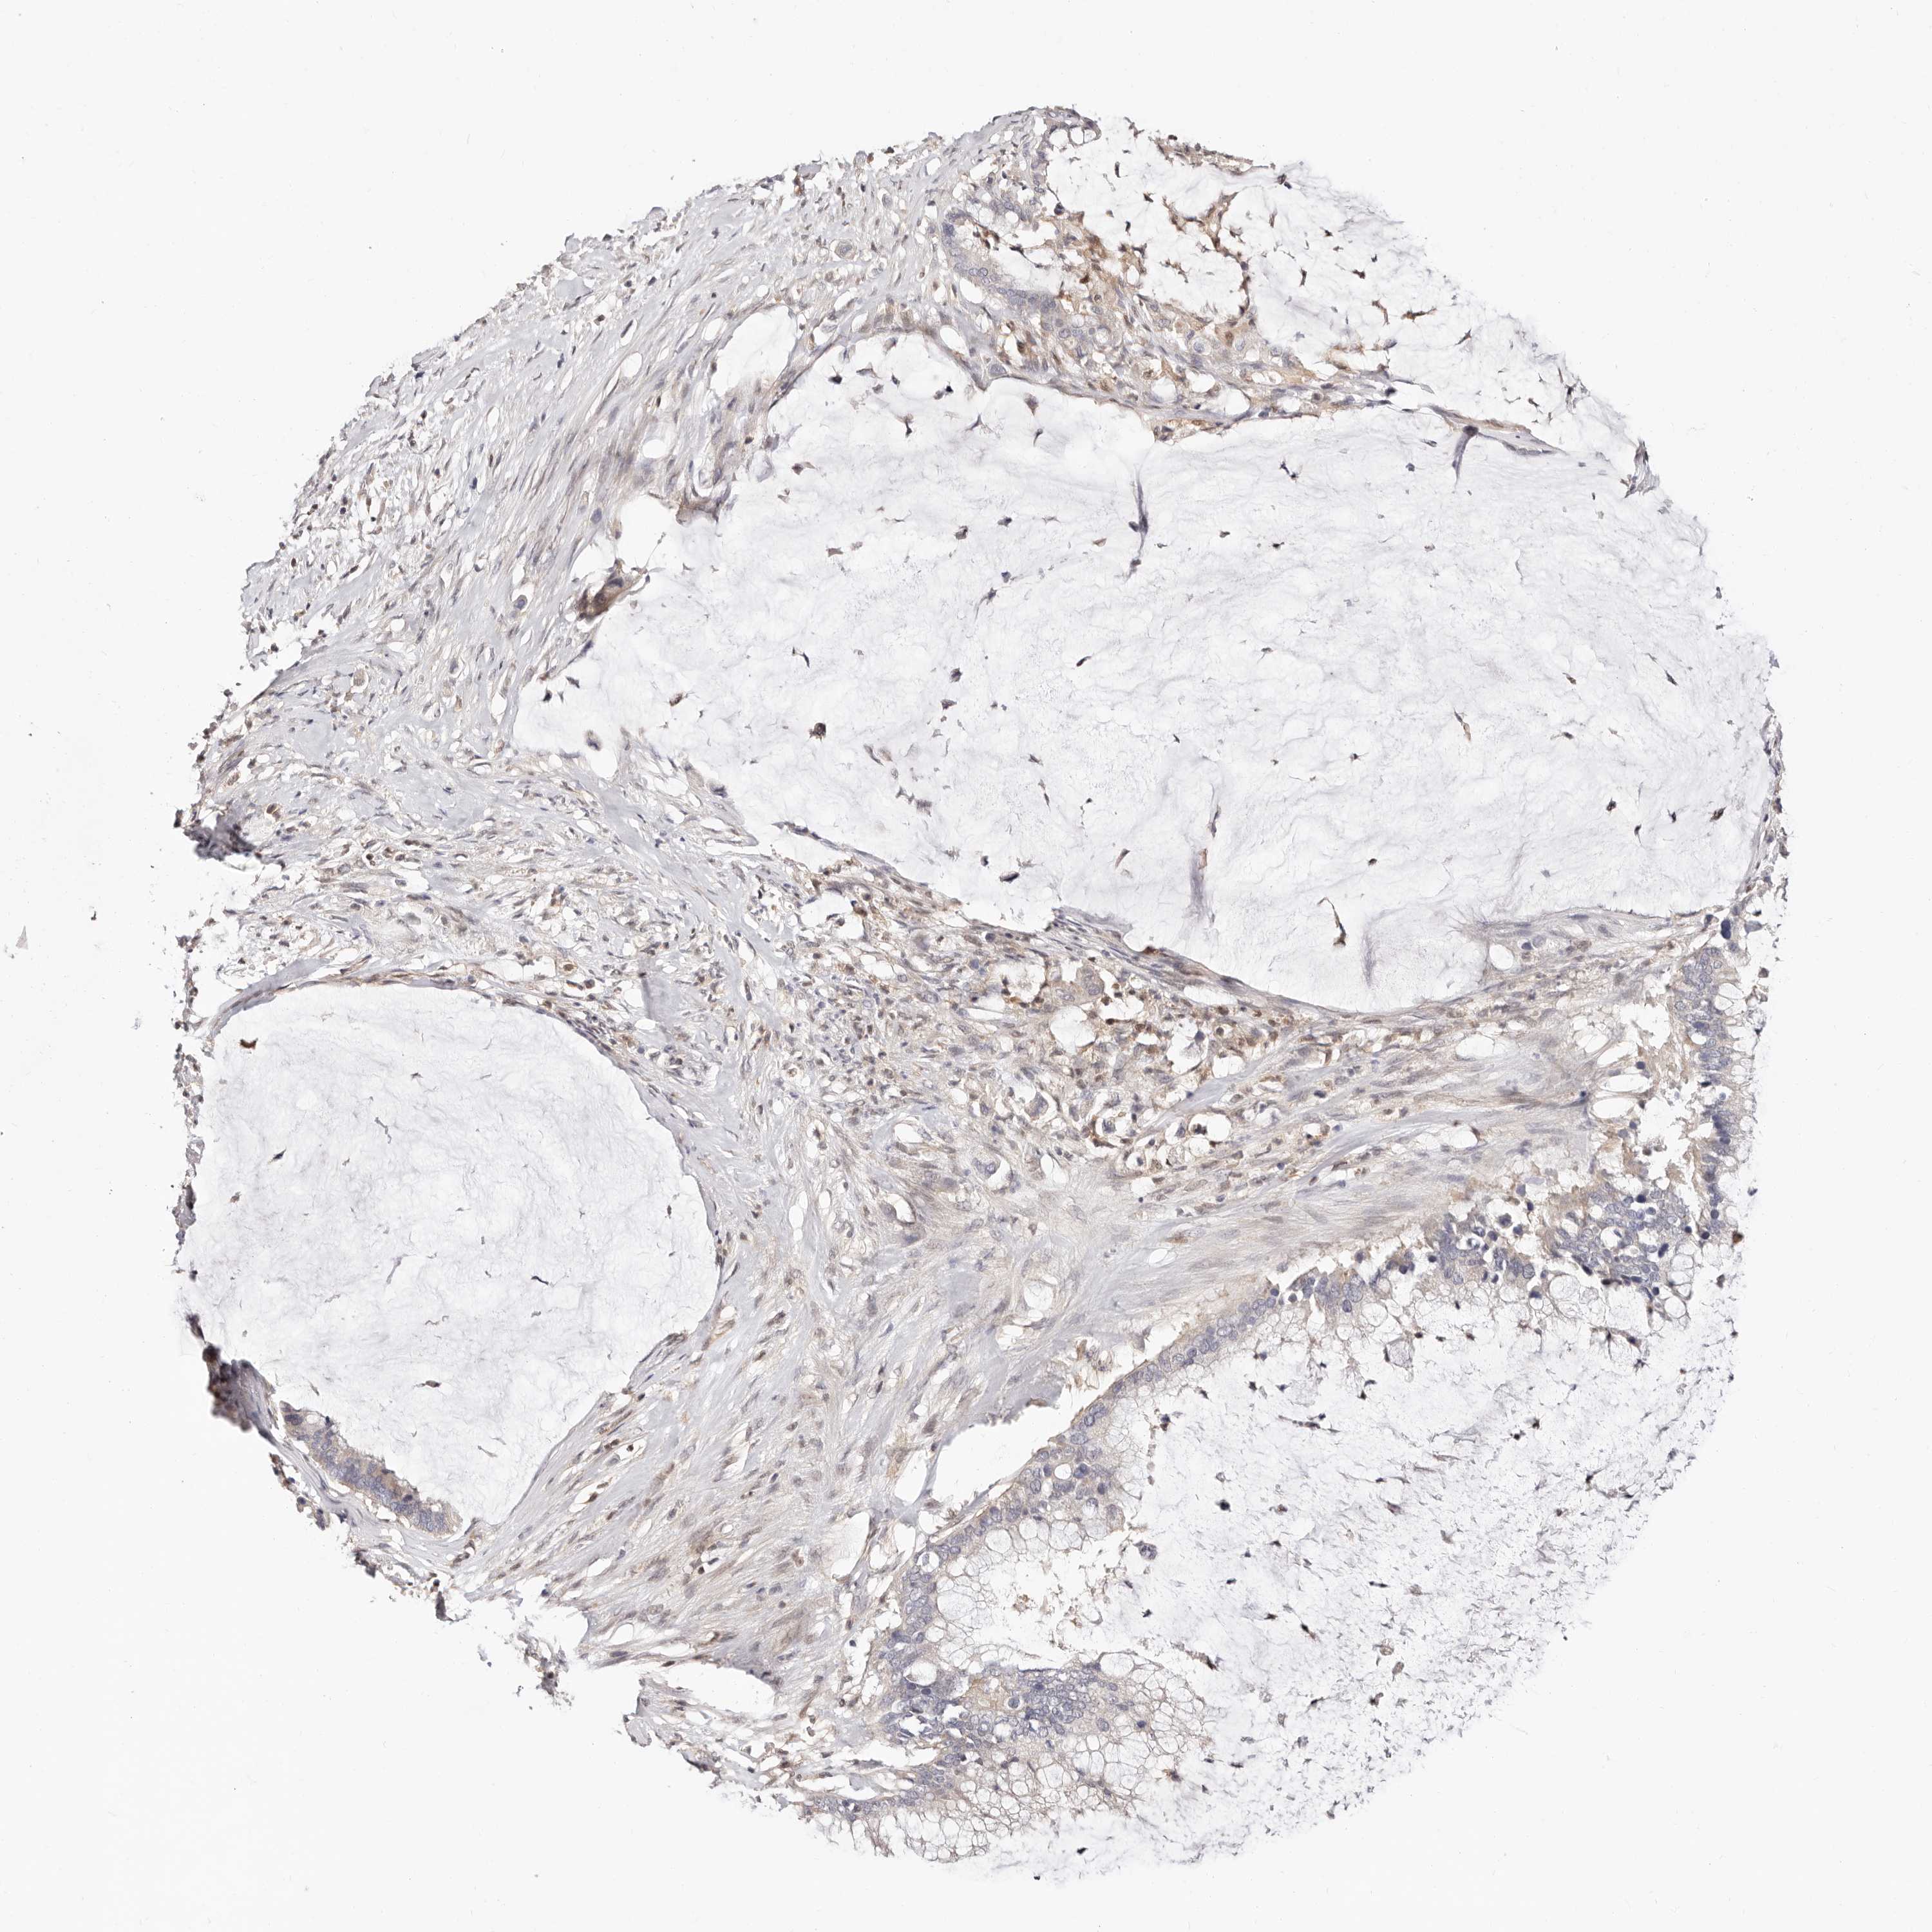

PANCREATIC CANCER - Protein expressioni

A mouse-over function shows sample information and annotation data. Click on an image to view it in a full screen mode. Samples can be filtered based on level of antibody staining by selecting one or several of the following categories: high, medium, low and not detected. The assay and annotation is described here.

Note that samples used for immunohistochemistry by the Human Protein Atlas do not correspond to samples in the TCGA dataset.

Antibody stainingi

Antibody staining in the annotated cell types in the current human tissue is reported as not detected, low, medium, or high, based on conventional immunohistochemistry profiling in selected tissues. This score is based on the combination of the staining intensity and fraction of stained cells.

Each image is clickable and will lead to virtual microscopy that enables deeper exploration of all samples and also displays staining intensity scores, fraction scores and subcellular localization as well as patient and tissue information for each sample.

HPA027873

HPA042128

HPA049883

HPA051156

CAB003860